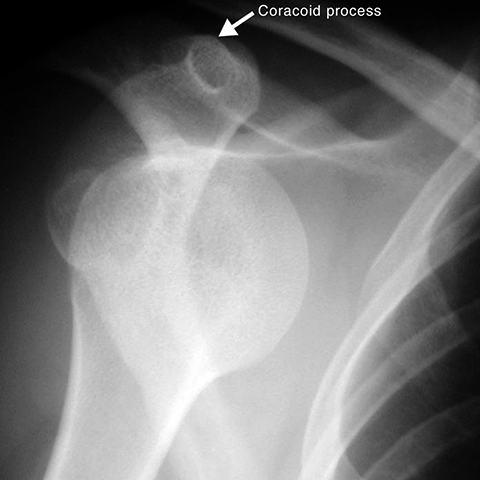

Glenohumeral dislocation